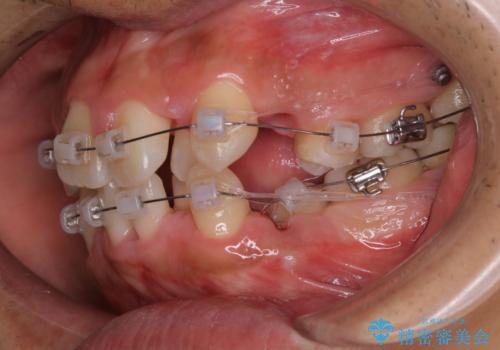

- ワイヤー装置で矯正中の方です。歯磨きがしずらく、専門的な機械でクリーニングしてほしいとの事でした。PMTC60分コースを行いました。

ワイヤー矯正中はブラッシングが難しくなるため、磨き残しが多くなることがあります。適切な道具を使って、適切なブラッシング方法を習得することで、磨き残しを減らすことができます。

また、矯正で歯の移動があると今までなかったところに隙間が出てきたり、ガタつきが解消されてきたりすることで、お口の中の環境が変わります。

矯正治療中も清潔な口腔内を保つことは、とても大切です。そのため、定期的に専門的な機械・材料を使用したProfessinnalcleaning(pmtc)を行うことがおススメです。